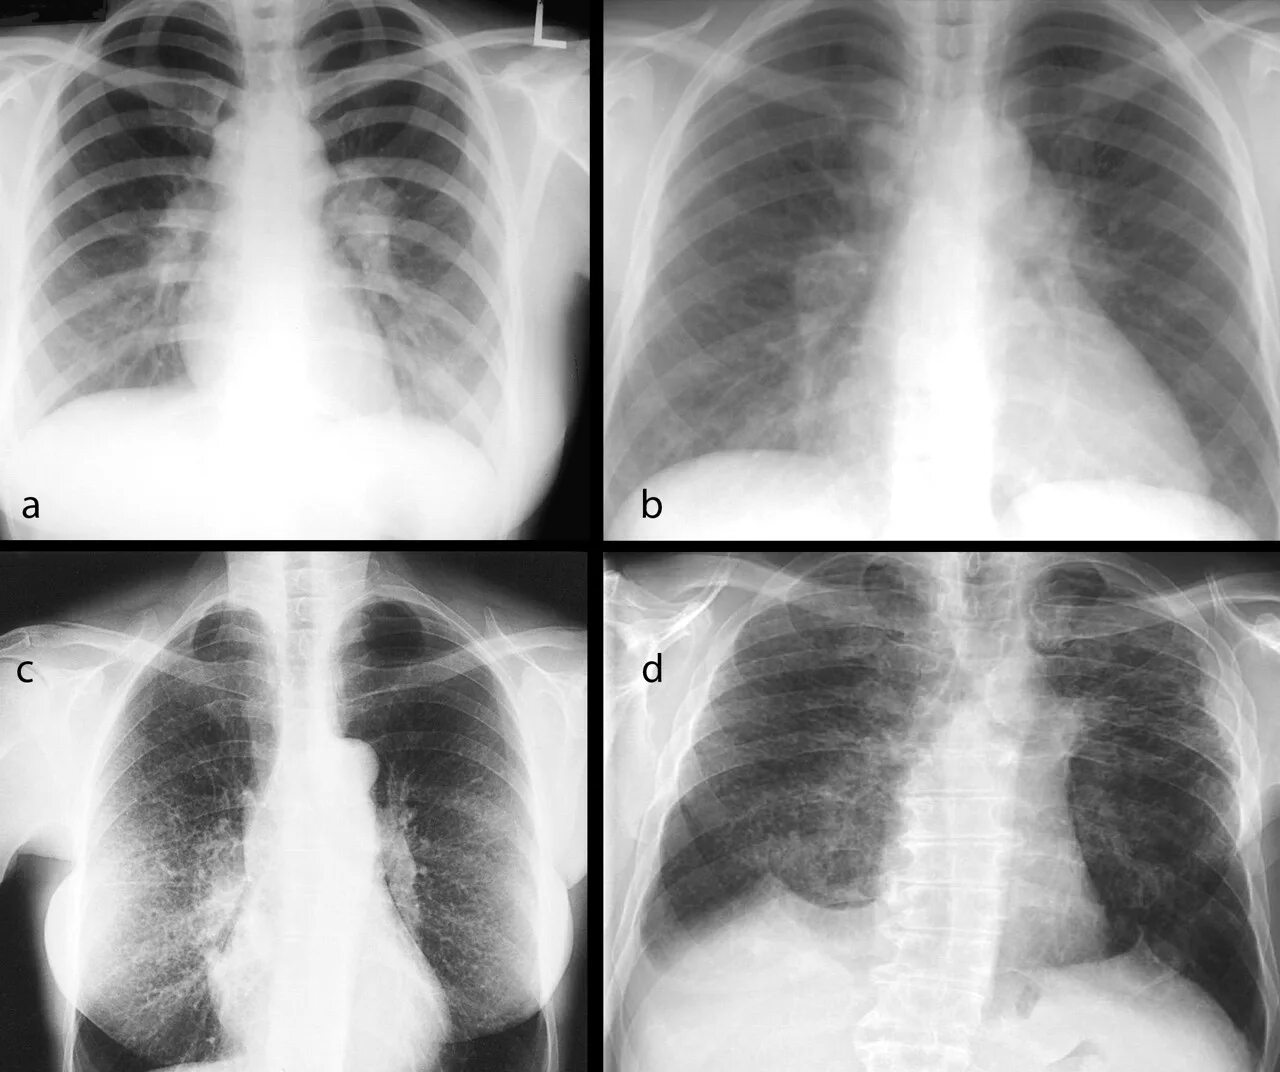

Саркоидоз 1